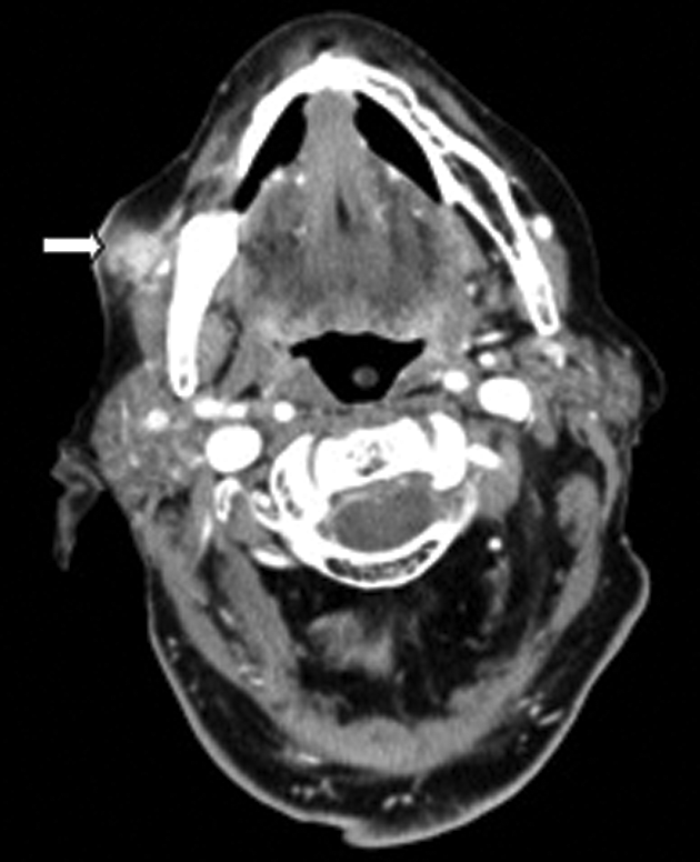

Clinical examination excluded a dental cause, as the patient was edentulous, however an ultrasound demonstrated an abscess over the right masseter muscle. Figure 3 shows an abscess collection in the right buccal space. Figure 4 demonstrates the cause of the abscess (and otalgia) - a tooth root buried underneath the gingiva, with associated buccal bone perforation.

Figure 3: Contrast enhanced soft tissue axial CT demonstrating a buccal space abscess (white arrow).